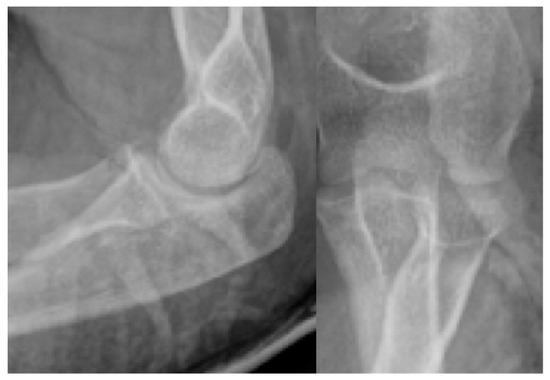

Second patient: A fifteen-year-old boy was admitted after he suffered a fall. The patient complained of pain and difficulty with weight-bearing. Knee extension was painful during the physical examination, and a hematoma could be felt in the suprapatellar bursa. Primary X-rays showed the osteochondral fracture of the patella, which was confirmed by CT imaging, with the broken piece in the lateral recess (Figure 4).

Figure 4.

CT images of the knee, showing the fragment (black arrow) and the location of the missing piece (red circle).

Third patient: A 17-year-old patient was admitted following a snowboarding injury that affected her elbow. Although the patient reported pain and swelling of the proximal forearm was visible upon inspection, the Moberg test was negative. The fracture of the radial head was confirmed by the initial X-ray, after which a CT was performed, which established a Mason type II fracture and dislocation of the radial head (Figure 7).

Figure 7.

The CT images confirm the Mason type II fracture and dislocation of the radial head.